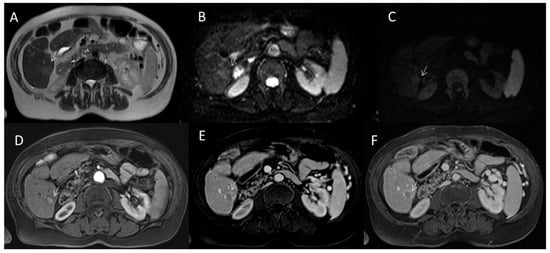

2.2.5. LR-M Category

2.3. CEUS-LI-RADS